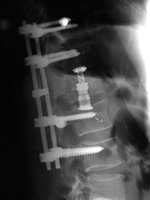

| Extensive lumbar spine fusion with pedicle screws and rods |

| A laminectomy has been performed from T12-L5. Pedicle screws and rods are at L3-S1 from the initial lower lumbar spine fusion. Later surgery added pedicle screws and rods at T12-L3, and L3-L5 with a crosslink at L2. |